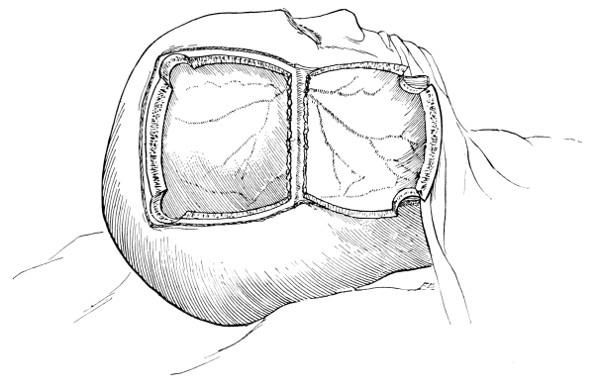

Fig. 18. Second Stage in the Formation of an Osteoplastic Flap. The bone-flap turned down and the dura mater exposed.

The dura is now separated from the bone along the line of the two vertical incisions, and the visceral blade of de Vilbiss’s forceps insinuated beneath the bone, starting at one trephine-hole and working downwards to the lower limit of the incision. It is essential that the operator should be satisfied with the ‘morcellement’ of small portions of bone at each bite of the instrument. At the lower end of each[28] of the vertical incisions the forceps is directed inwards for 1⁄4 to 1⁄2 inch so as to weaken the base of the flap.

To lift up the osteoplastic flap, a stout elevator or spatula is introduced beneath the bone at its upper part, leverage applied, and, as soon as sufficient elevation has been attained, the dura mater carefully separated from the whole of the under aspect of the flap. The flap is then grasped at its upper part with both hands and, with a quick but forcible jerk, broken across at its base, the assistant at the same time aiding the correct linear fracture of the bone by a flat spatula applied to the outer aspect of the base of the flap. Insomuch as the flap is most usually framed in the parieto-temporal region—for the exposure of the motor area—the base of the flap, being formed from the squamous portion of the temporal bone, is comparatively weak. Fracture is then readily obtained. Under other circumstances the base may be sufficiently weakened by the application of the de Vilbiss forceps or by the use of the Gigli saw.

The bone-flap is thrown back and enveloped in gauze. Its basal region is examined for a possible injury to meningeal vessels. In the event of such complications the bleeding vessel is clipped, ligatured, or underrun. Possibly some branch of the anterior division of the middle meningeal artery, running in an osseous canal, may require to be controlled by foraminal occlusion—with a wooden match, bone peg, cotton-wool, or aseptic wax.